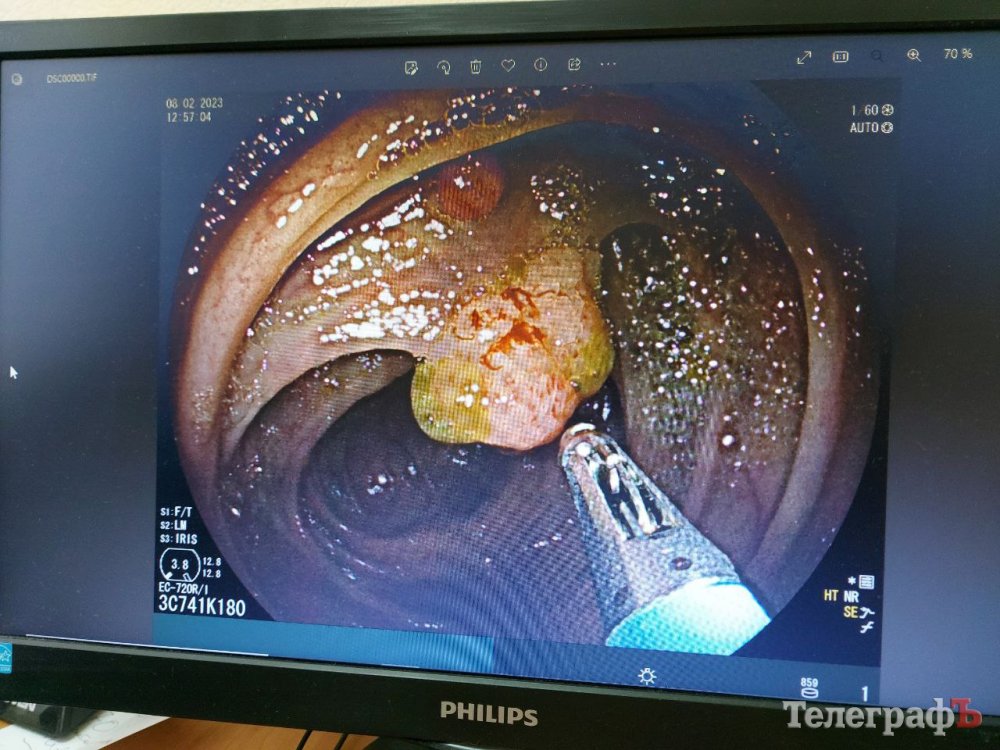

Якщо під час обстеження фахівець знаходить утворення – поліп, виразку чи пухлину, тоді беруть біопсію («відщипують» шматочок слизової оболонки й направляють його на гістологічне дослідження).

– За допомогою апарату високої роздільної здатності ми можемо на основі знань виставити попередній оптичний діагноз – чи то доброякісний, чи то передпухлинний поліп із початком переродження. Але ракові клітини можуть ховатися в глибині цього поліпу, а ми беремо шматочок зверху.

Гістологи дивляться під мікроскопом цей шматочок, з’ясовують, які клітини там, і від цього залежить подальша тактика ведення пацієнта. Лікар-гістолог дає своє заключення. Якщо аденоматозний чи гіперпластичний поліп, то вони підлягають плановому ендоскопічному видаленню, – пояснює ендоскопіст. – Але якщо там є зміни, то вони підлягають консультуванню у лікаря-онколога.

Коли виявляють, наприклад, поліп, який підлягає оперативному ендоскопічному втручанню, його можна видалити методом поліпектомії («холодною» або «гарячою» петлею).

Методом поліпектомії поліп можуть одразу видалити й віддати його на гістологічне дослідження, адже проблема у ньому може бути не лише зверху, а й глибше.